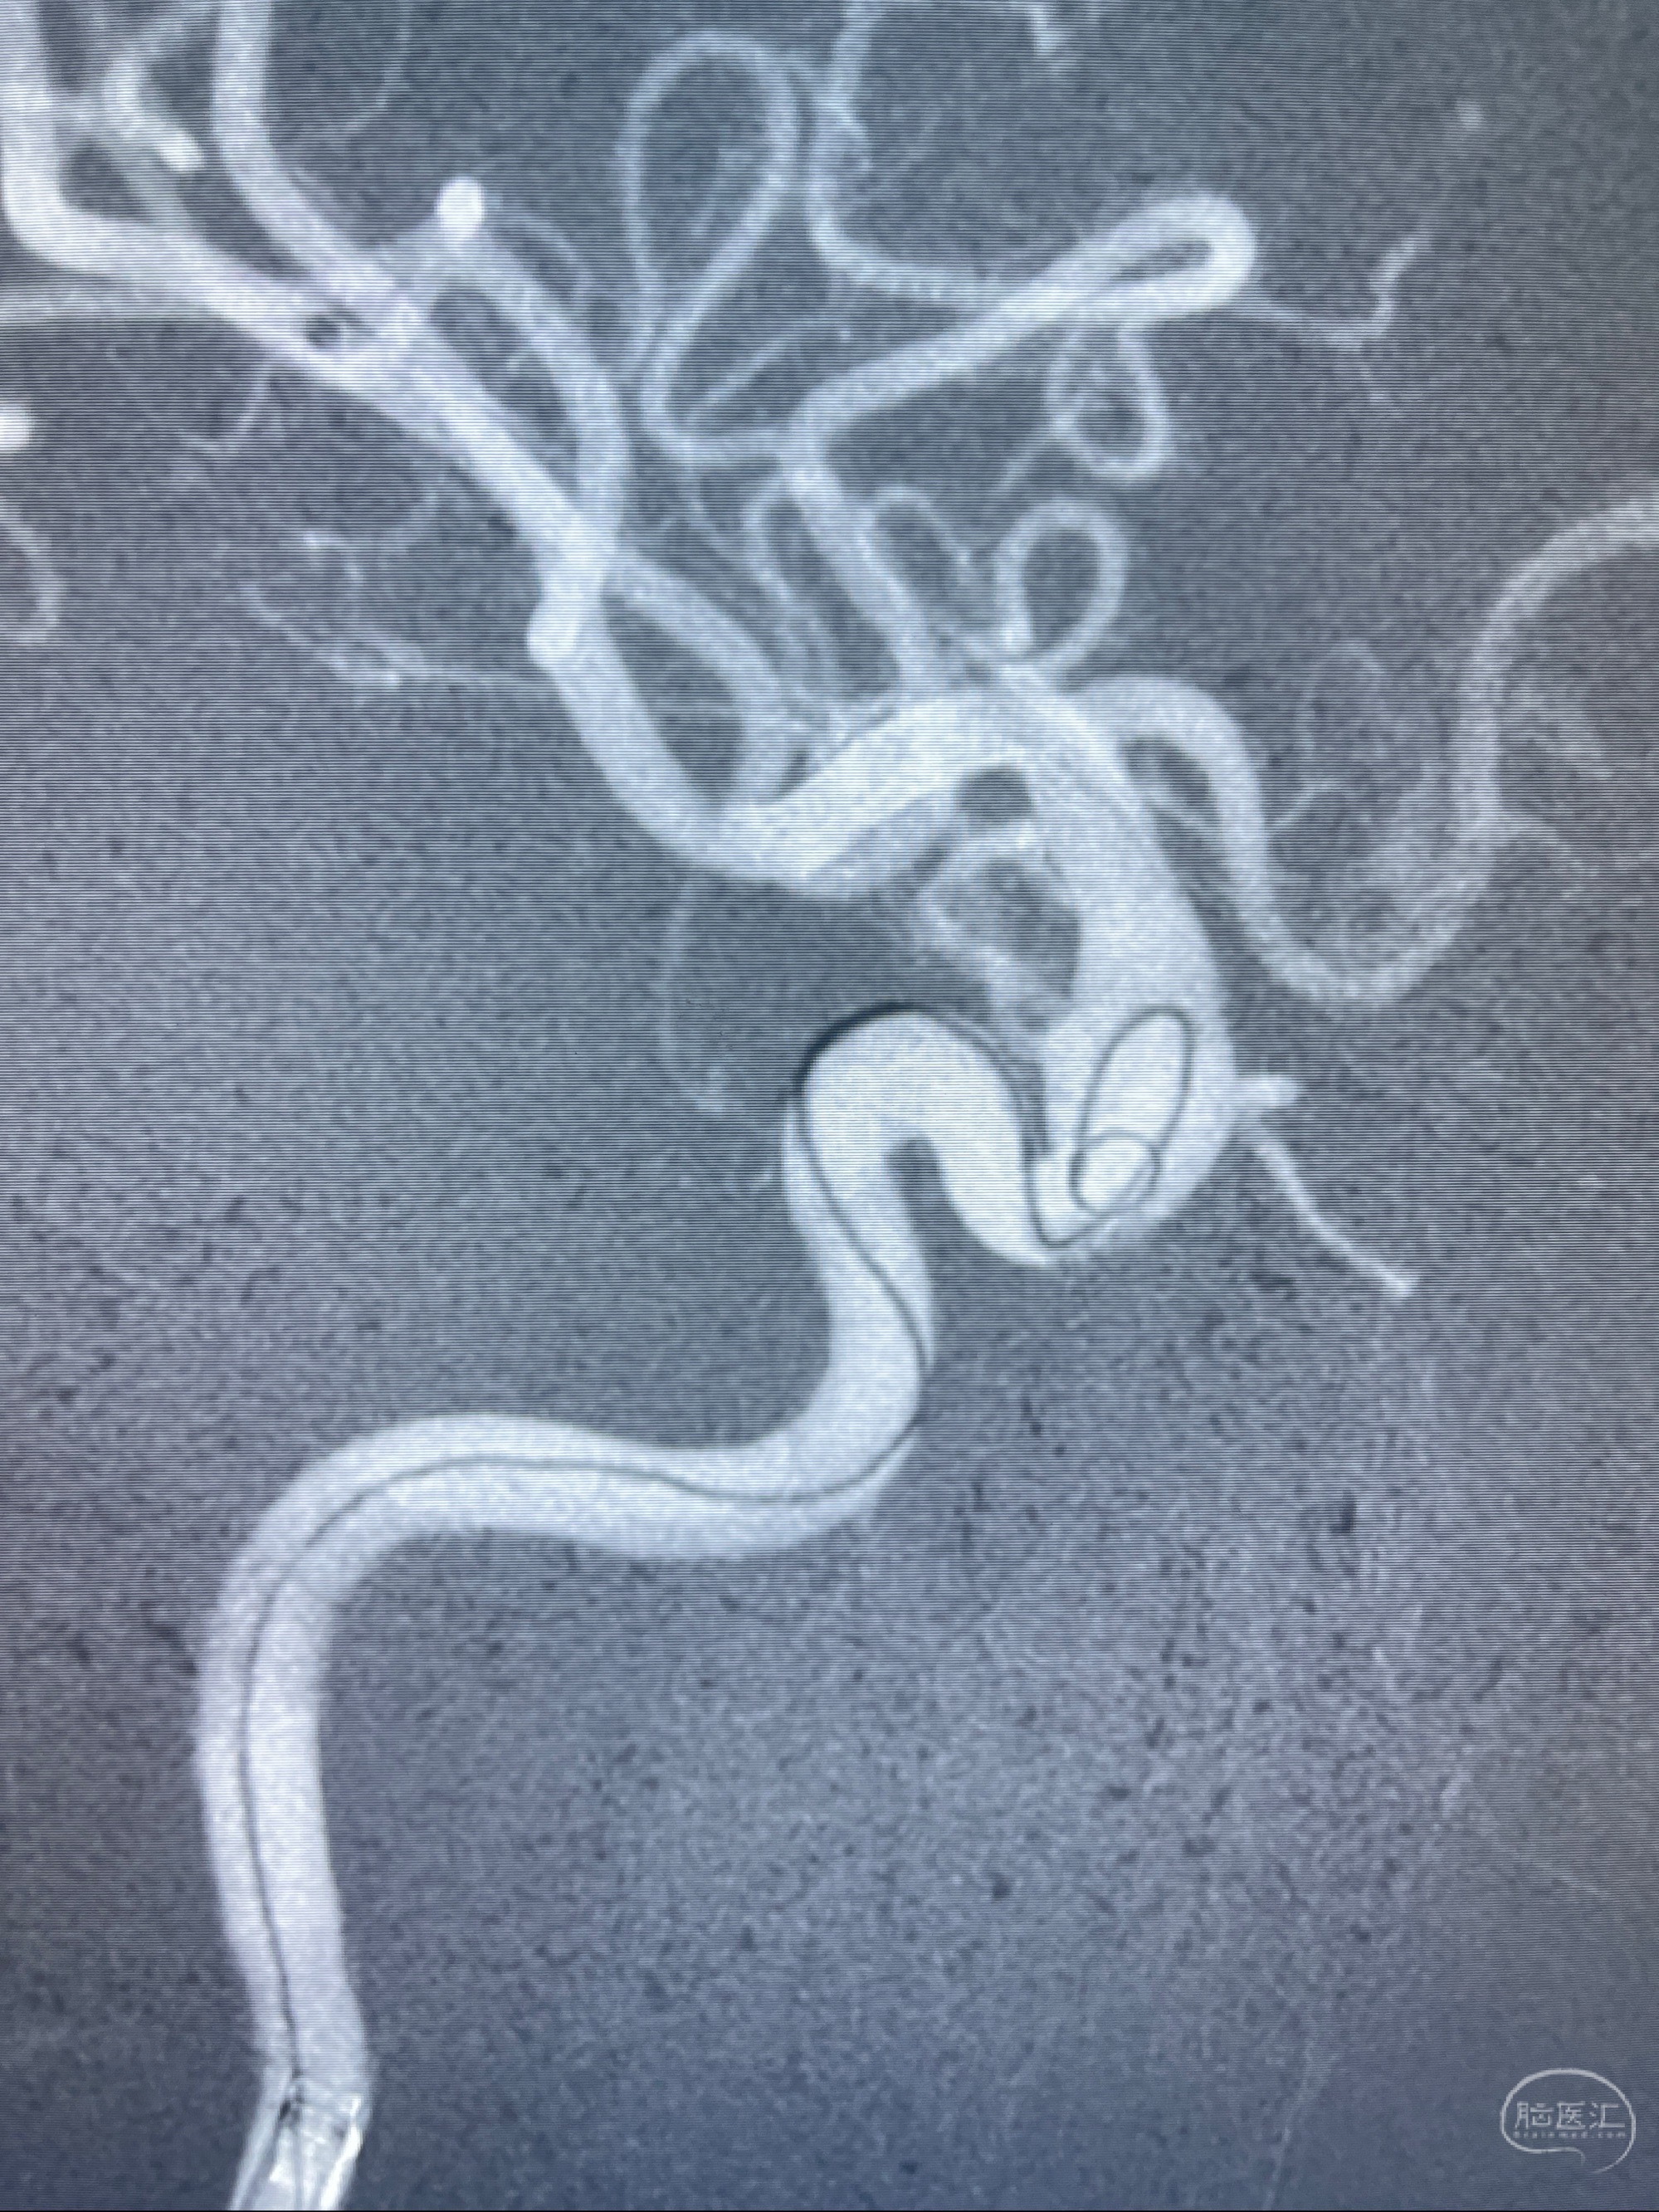

2023-07-27全脑血管造影:双侧颈内动脉眼动脉段动脉瘤,右侧较大

2023-08-01全麻下行双侧颈眼动脉瘤支架辅助栓塞

- pipeling4.5-20mm

- pipeline 4.0-20mm

手术顺利,麻醉苏醒佳,遵嘱动作